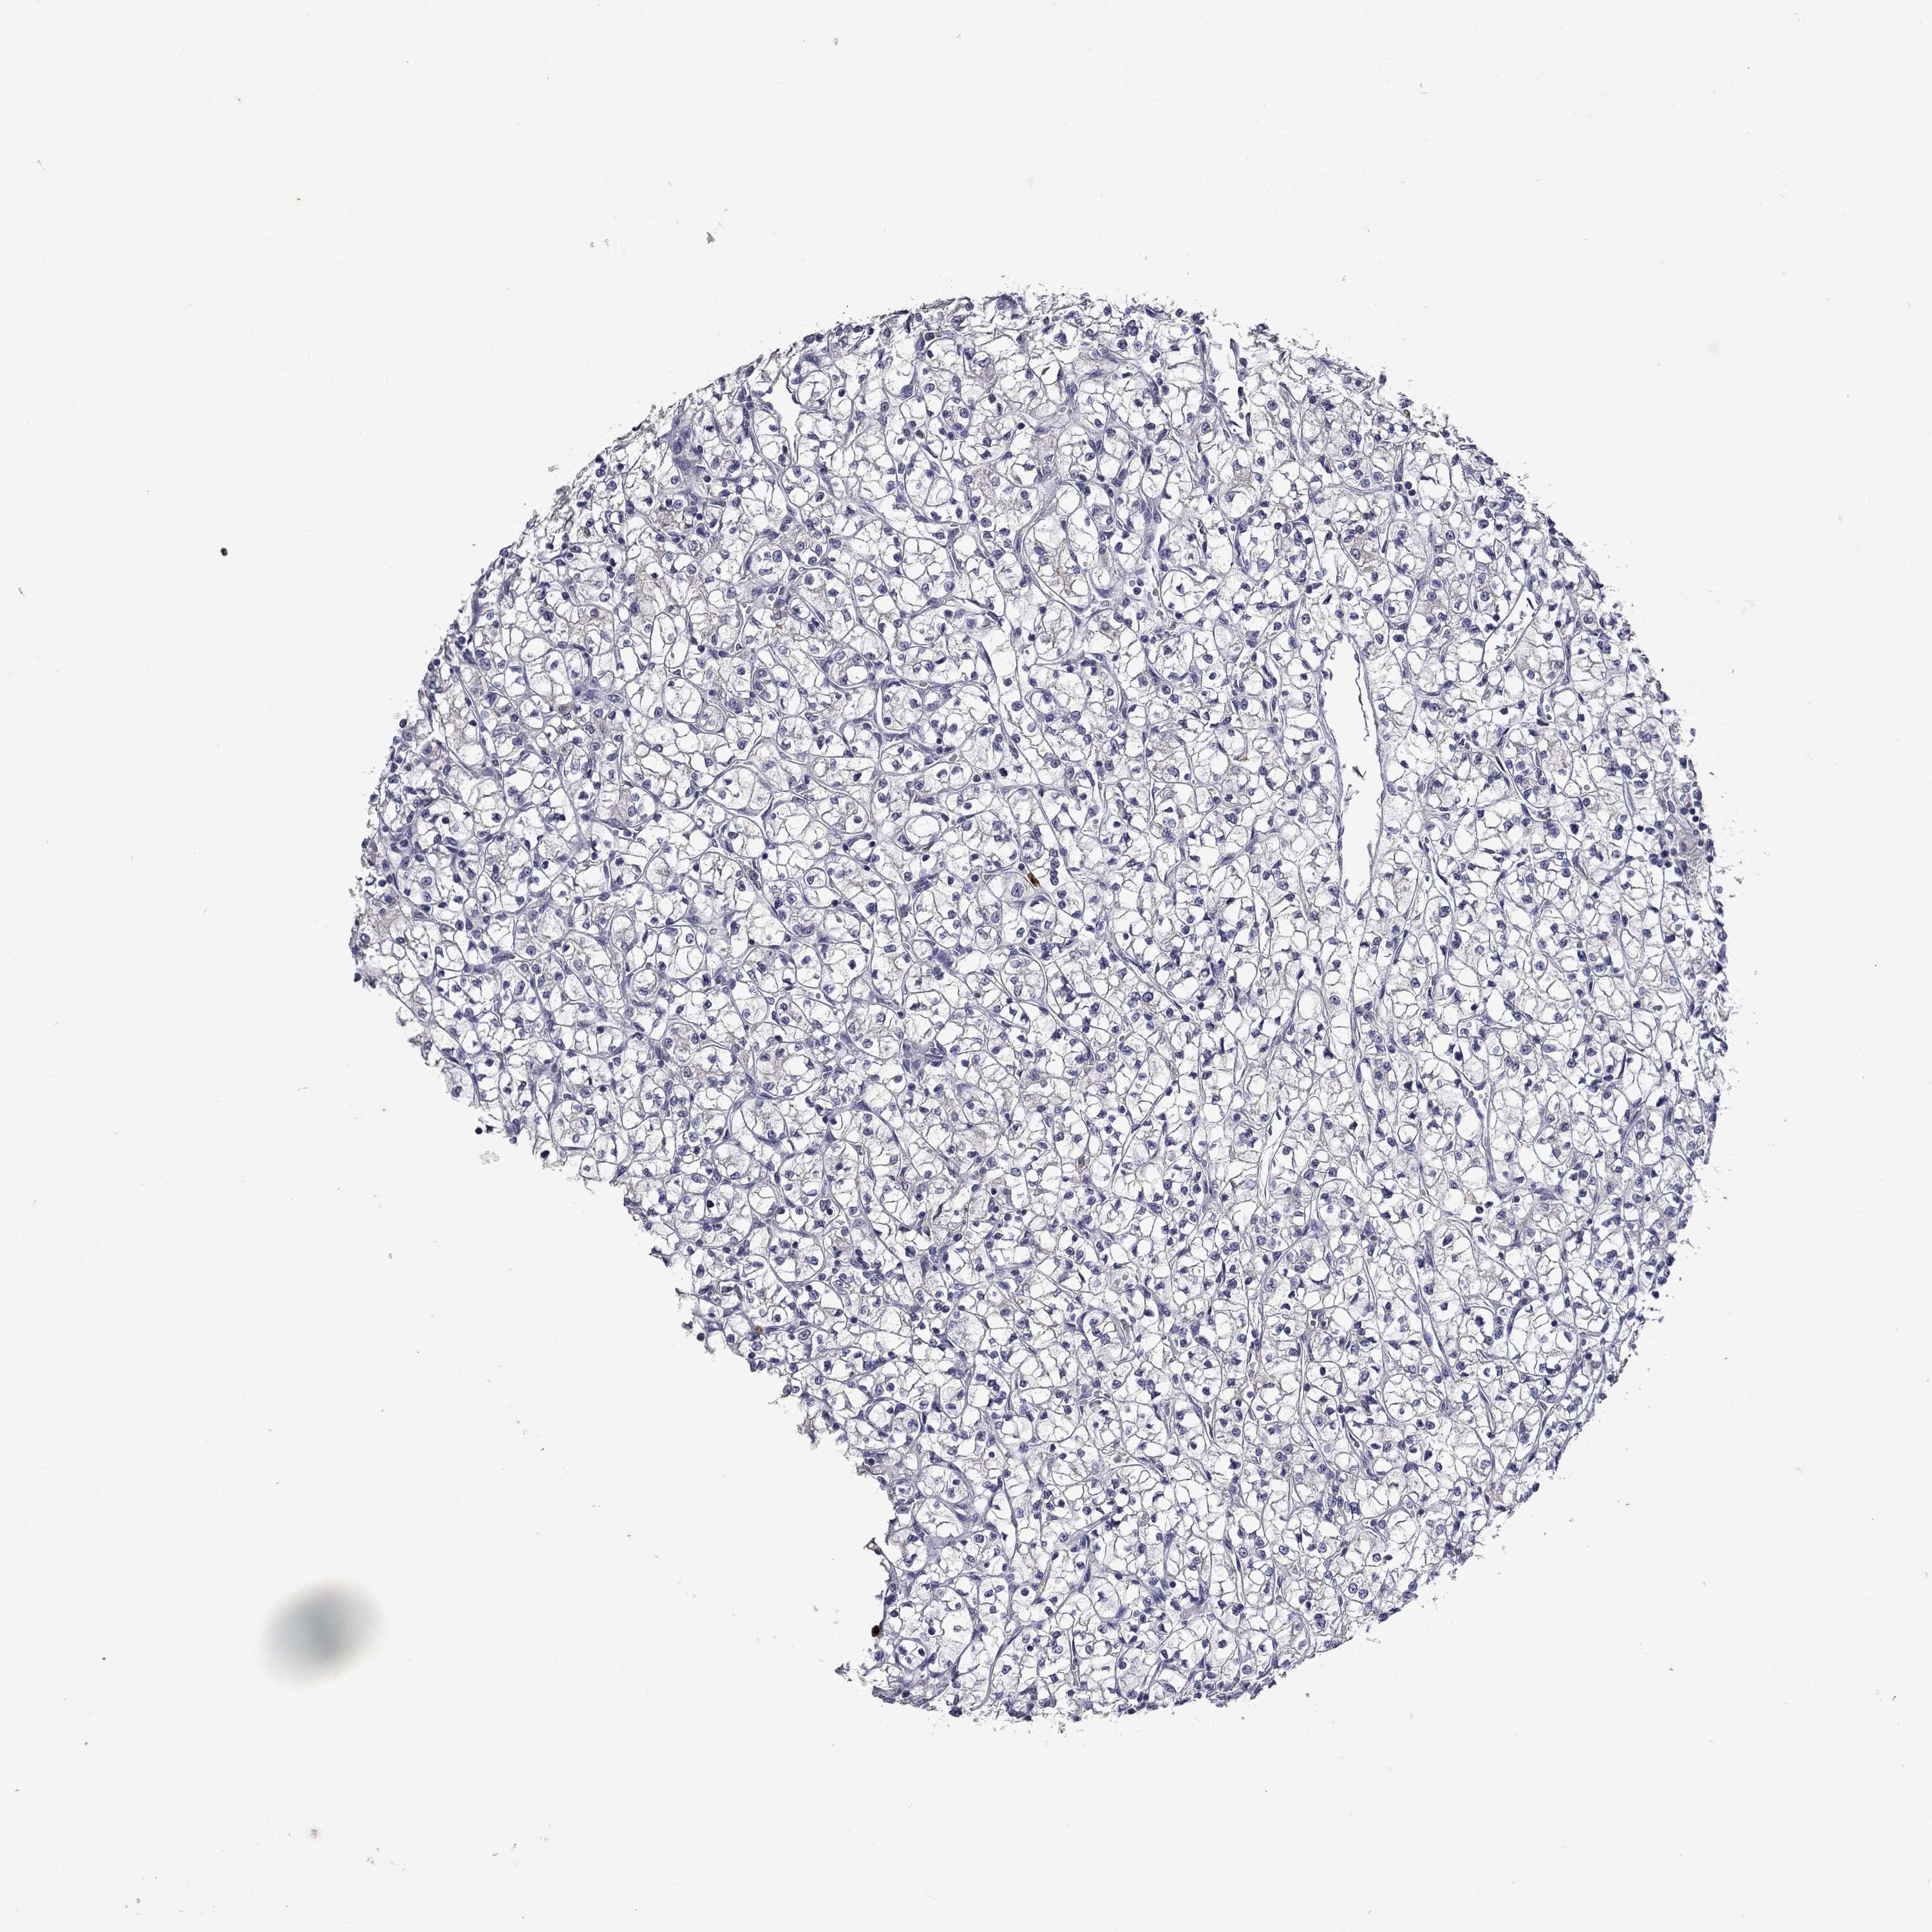

Average pTPM 9.9

Number of samples 521